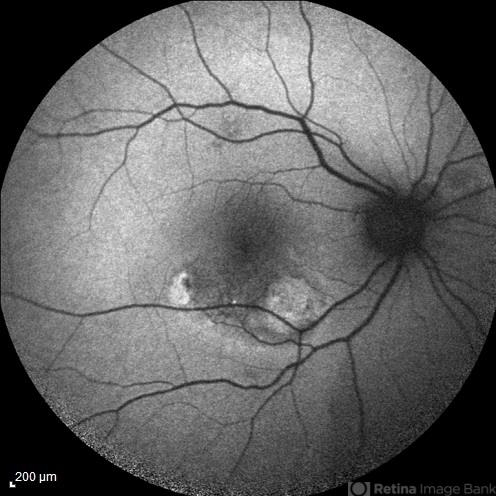

- polypoidal choroidal vasculopathy (PCV), fundus autofluorescence (FAF)

- FAF image of the right eye of a 55-year-old woman with decreased vision and metamorphopsia due to PCV.